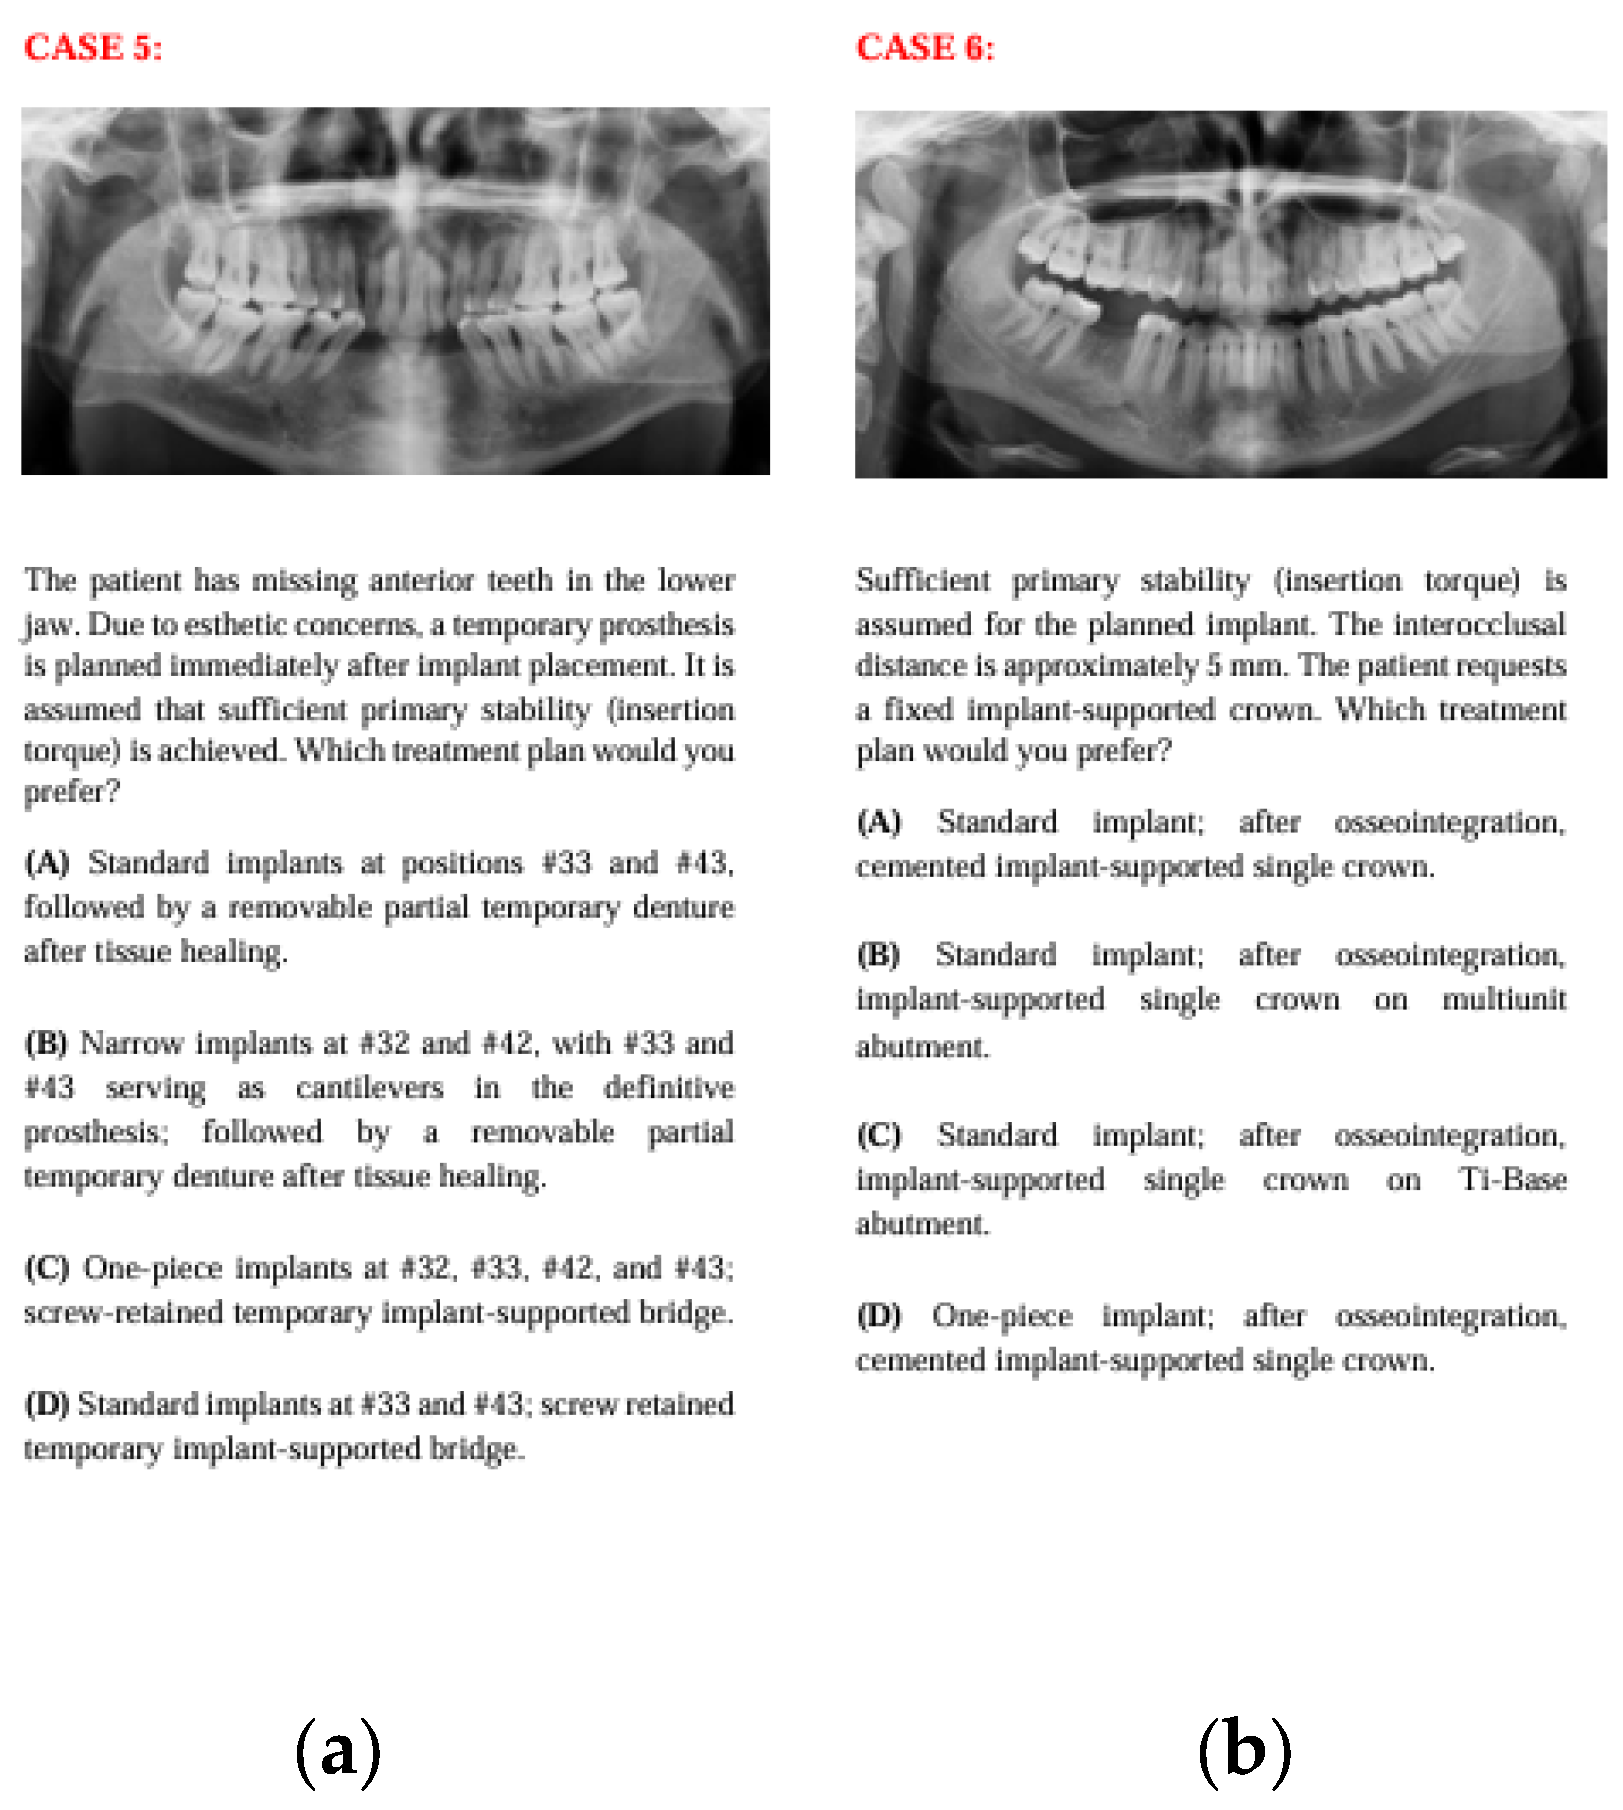

Figure 6. The panoramic radiographs, descriptions, and four treatment options of Case 11 (a) and Case 12 (b).

In Case 11, where the case involved anterior esthetics and immediate implantation, clinicians predominantly chose options C and D, while AI chose option A. This may be because clinicians aimed to avoid the risk of placing implants across the entire area in an anterior region with a history of lesions or, guided by clinical intuition, leaned toward treatments with fewer implants or plans like option D that involve waiting for osseointegration to reduce complications. AI, on the other hand, may have leaned toward option A, which aligns with the current literature emphasizing the success of immediate implantation with immediate provisional prostheses in the esthetic zone, aiming to place as many implants as possible.

In Case 12, although option C was the most preferred across all groups, a significant distribution difference was found between human and artificial intelligence. In this question evaluating abutment types in single-implant restorations, clinicians, based on varied clinical experiences, opted for different choices, whereas AI consistently preferred single crown restorations on Ti-base abutments, which are frequently highlighted in the recent literature.